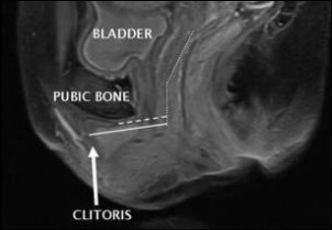

Известно, что наиболее чувствительная зона женского тела – клитор. Как выяснилось, его размер имеет огромное значение. Те женщины, у которых были проблемы с оргазмом, этот орган намного меньше и находится дальше от влагалища.

Сравнивая результаты, американские эксперты из Цинциннати обнаружили, что расстояние между клитором и влагалищем, было на 5-6 см. больше у тех женщин, кто не получал оргазма. Эти же представительницы слабого пола обладали меньшим, по размеру, клитором.